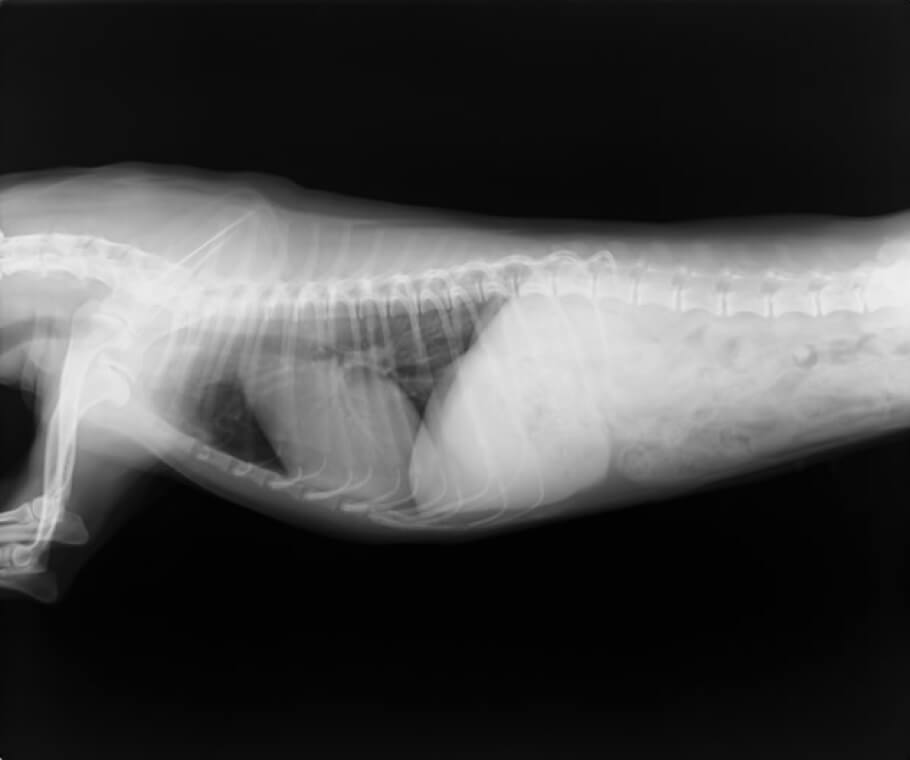

胸部レントゲン検査

X線により心拡大の有無、気管や肺の異常・病変の有無、肝臓うっ血の有無など、内臓の外観の評価を行います。2~3方向から撮影することによって多角的に異常を検出します。

心臓疾患による外観の異常は、たとえば咳の症状が見られた場合には肺や気管にも変化が見られるなど、心臓以外にも現れることがあります。胸部レントゲン検査はスクリーニング検査としても、診断の確度を上げる意味でも重要です。また、犬猫の心臓疾患は肺水腫や胸水を二次的に引き起こすことが多いため、その確認をする上でも有用となります。

正常心陰影(小型犬)

心拡大、肺水腫(小型犬)